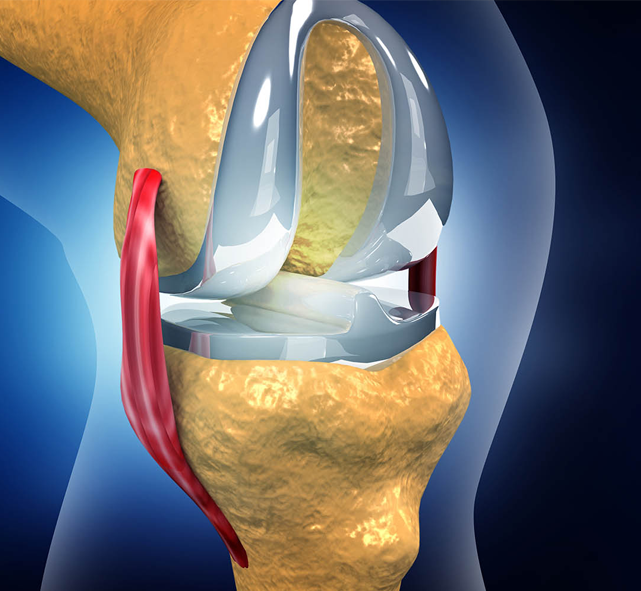

Anatomy

The foot and ankle are vulnerable to a variety of conditions that can affect mobility, comfort, and overall quality of life. These issues may involve bones, joints, ligaments, tendons, or soft tissues, leading to pain, instability, or deformities. Common conditions include: